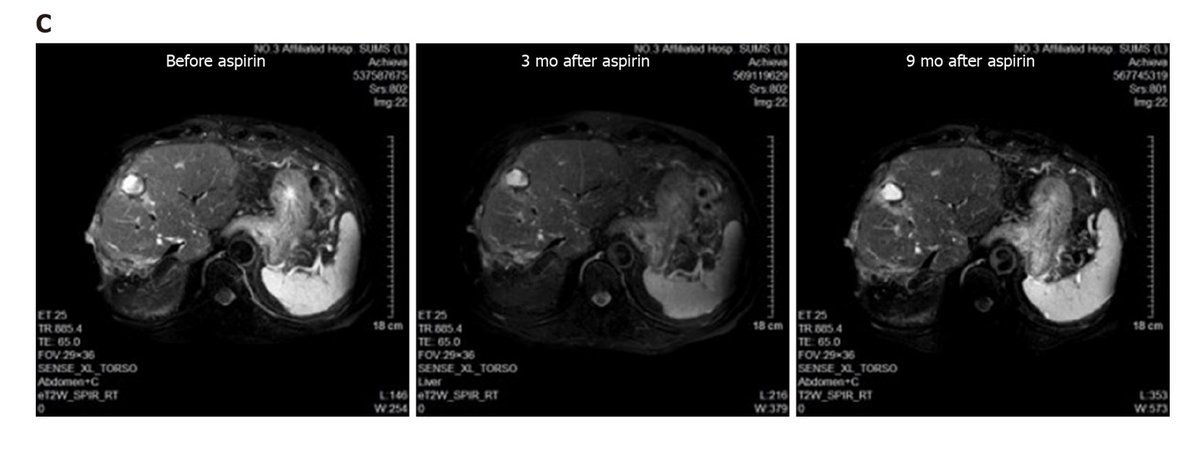

What if I told you that a treatment that costs literally one nickel per day could completely reverse an otherwise deadly liver cancer?

Aspirin did that.

Aspirin did that.

In fact, aspirin has consistently and unequivocally shown to reduce both the incidence AND the mortality of various cancers.